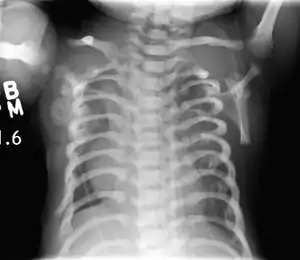

CXR of a newborn with asphyxiating thoracic dysplasia. Note the short ribs.

Asphyxiating thoracic dysplasia (ATD), also known as Jeune syndrome, is a rare inherited bone growth disorder (autosomal recessive skeletal dysplasia) [1] that primarily affects the thoracic region. It was first described in 1955 by the French pediatrician Mathis Jeune.[2] Common signs and symptoms can include a narrow chest, short ribs, shortened bones in the arms and legs, short stature, and extra fingers and toes (polydactyly). The restricted growth and expansion of the lungs caused by this disorder results in life-threatening breathing difficulties; occurring in 1 in every 100,000-130,000 live births in the United States.[1][3]

Jeune syndrome is a rare genetic disorder that affects the way a child’s cartilage and bones develop. It begins before the child is born and primarily affects the child's rib cage, pelvis, arms and legs.[5] Usually, problems with the rib cage cause the most serious health problems for children with Jeune syndrome. Their rib cages (thorax) are smaller and narrower than usual, which inhibits the child's lungs from developing fully or expanding when they inhale. The child may breathe rapidly and shallowly. They may have trouble breathing when they have an upper or lower respiratory infection, like pneumonia. Breathing trouble can range from mild to severe. In some children, it is not noticeable, aside from fast breathing; however, in others, breathing problems can be fatal. About 60% to 70% of children with this condition die from respiratory failure as babies or young children. Children with Jeune syndrome who survive often develop problems with their kidneys, and over time they may experience kidney failure.[2] As a result, few children with Jeune syndrome live into their teen years. Children with Jeune syndrome have a form of dwarfism. They are short in stature, and their arms and legs are shorter than most people’s.[6]